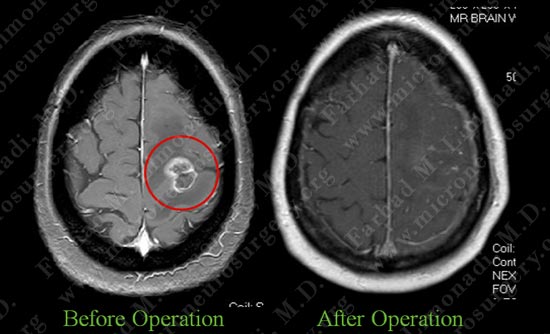

MRI scan of patient's brain shows a tumor within the motor cortex gyrus.

Post op MRI shows complete resection of the tumor with no injury to surrounding neuro-vascular structures. Most importantly patient had no neurological deficit after the operation.